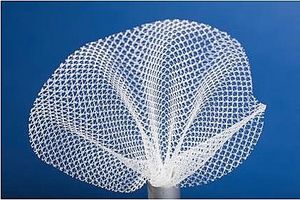

... Implantierbares Mesh-Gerät zur Wandverstärkung und lang anhaltenden Stabilisierung. CRISTALENE bietet - Weitporiges Netz, das das Infektionsrisiko reduziert - Polypropylen-Monofilamente, die eine gute Gewebeintegration ermöglichen und ...

ABISS